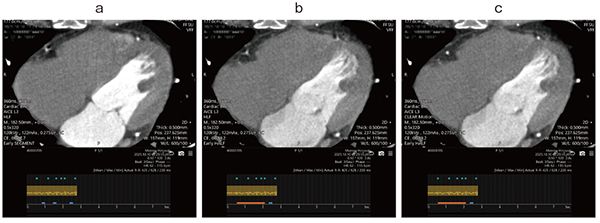

図2 心房細動

アブレーション術前肺静脈造影CT。心拍コントロールせず、複数ビート撮影。セグメント再構成(a)ではモーションアーチファクトが目立つが、1ビートによるハーフ再構成(b)にCLEAR Motionを使用することで、モーションアーチファクトの少ない画像が取得できた(c)。左房の評価目的であったが冠動脈の評価も可能となった。